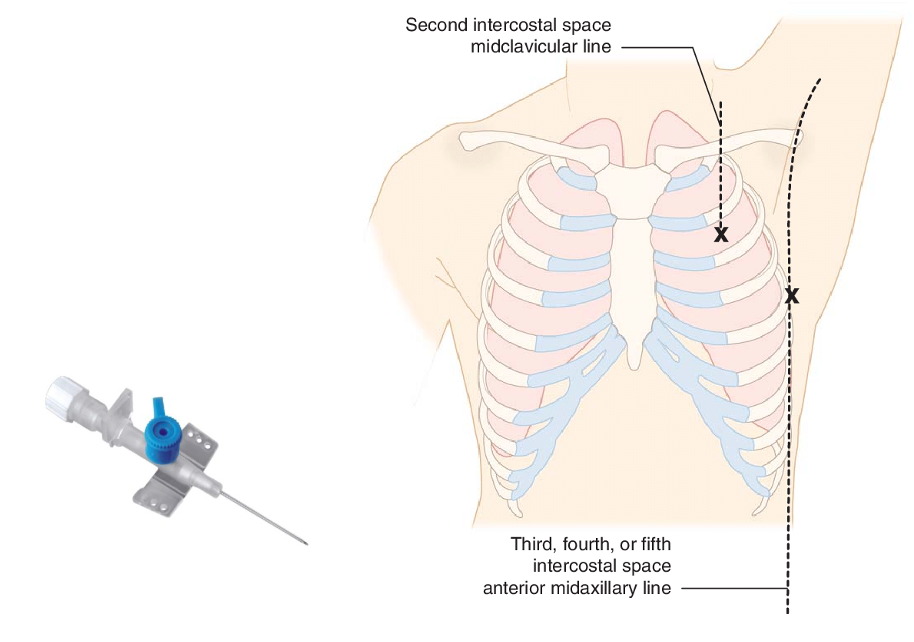

In symptomatic patients:

- A 22-gauge angiocatheter is placed perpendicularly to the chest wall in the 2nd intercostal space in the midclavicular line or in the 5th intercostal space in the midaxillary line.